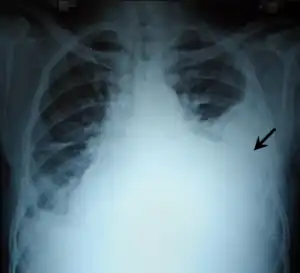

| Chest X-ray showing left sided hemothorax (arrowed) | |

A chest X-ray is the most common technique used to diagnosis a hemothorax.[23] X-rays should ideally be taken in an upright position (an erect chest X-ray), but may be performed with the person lying on their back (supine) if an erect chest X-ray is not feasible. On an erect chest X-ray, a hemothorax is suggested by blunting of the costophrenic angle or partial or complete opacification of the affected half of the thorax. On a supine film the blood tends to layer in the pleural space, but can be appreciated as a haziness of one half of the thorax relative to the other.[5] A small hemothorax may be missed on a chest X-ray as several hundred milliliters of blood can be hidden by the diaphragm and abdominal viscera on an erect film. Supine X-rays are even less sensitive and as much as one liter of blood can be missed on a supine film.[24]